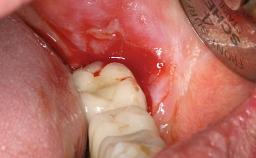

A 31-year-old man presented to our clinic 30 days after a motor vehicle accident in which he had suffered a dentoalveolar fracture in the anterior maxilla, including avulsion of teeth 12 and 11 and luxation of tooth 21. He was first treated on the night of the accident in a small city hospital with no oral and maxillofacial surgeon on the staff. A wired retention had been applied and the teeth repositioned to the best of the clinicians’ abilities. When he first presented to our care, the patient showed extrusion of teeth 12 and 11 associated with gingival recession due to bone loss in the anterior maxilla, and the stainless steel wires were still present.